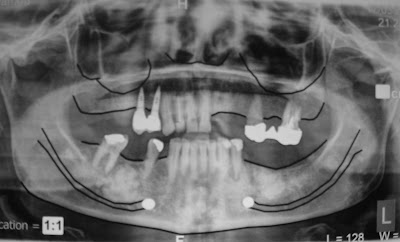

More Implants for a happy patient